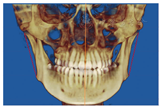

18、28、48阻生。牙根及牙槽骨未见明显吸收,下颌前牙唇舌侧骨皮质较薄(图2)。骨性Ⅲ类,上颌骨发育不足,高角,开

趋势较大。上切牙唇倾度正常,下切牙舌倾(表1)。锥形束CT影像检查发现双侧颞下颌关节形态不规则,皮质骨连续(图3)。舌体下沉。三维重建示双侧下颌升支长度不对称(图4)。